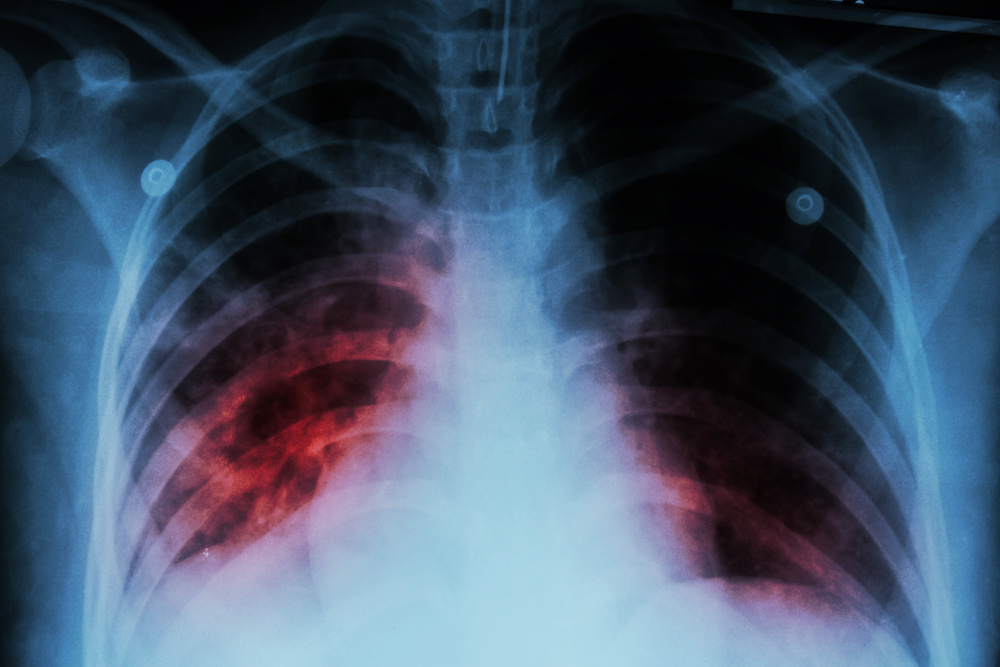

Le cas clinique rapporté est celui d’un patient de 30 ans diagnostiqué avec une infection par le VIH, mis sous ART, qui va rapidement développer une tuberculose pulmonaire. L’apparition d’une douleur, d’un érythème et d‘un gonflement au niveau du genou gauche 1 mois plus tard va conduire à un diagnostic de thrombose veineuse profonde. L’originalité de ce cas réside dans la coexistence de trois diagnostics, un sida, une thrombose et une tuberculose pulmonaire.

Une infection par le VIH multiplie par un facteur de 2 à 10 le risque de thrombose veineuse, comparé à ce qu'on observe dans la population générale. L'incidence moyenne en Europe serait de 131 cas/10.000 personnes/an. Les facteurs connus pour favoriser la VTE chez les patients VIH+ sont un taux de cellules CD4 faible, la présence d'un sida clinique, une déficience en protéine S et en protéine C. En parallèle, les patients VIH/sida ont un risque majeur de contracter une tuberculose pulmonaire. Cette étude rapporte pour la première fois la coexistence chez un même patient d'un sida, d'une tuberculose pulmonaire et d'une thrombose veineuse profonde.